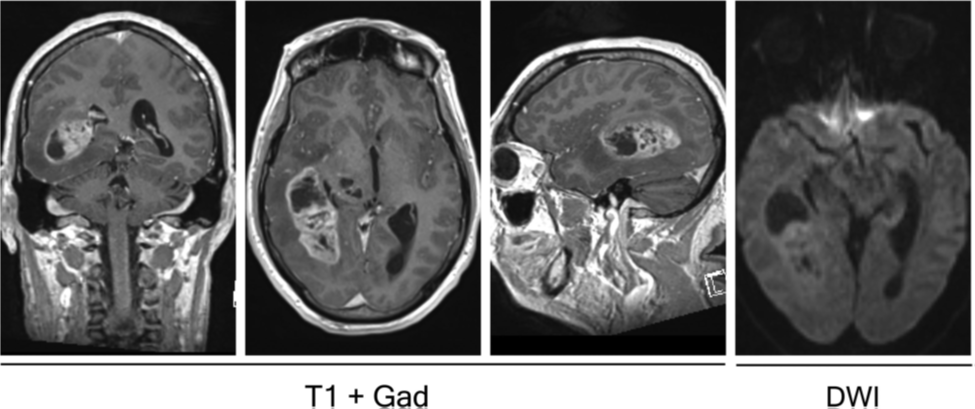

Hình ảnh của u nguyên bào thần kinh đệm trên phim MRI thể hiện những thay đổi vi môi trường điển hình cho quá trình phát triển của u nguyên bào thần kinh đệm. Bao gồm hình ảnh nhiều vùng hoại tử cũng như phù nề và các mạch máu u tân sinh bị dò (leaky tumor vessels), do đó u có hình ảnh bắt thuốc tương phản mạnh ở ngoại vi, và thường đi kèm vùng hoại tử trung tâm không bắt thuốc. Tất cả các yếu tố này kết hợp lại tạo ra những đặc điểm vi môi trường chỉ có ở u nguyên bào thần kinh đệm, và những đặc điểm này cực kỳ tương phản với nhu mô não bình thường khi phân tích về mặt mô học. Trong khi CT scan chỉ là phương tiện chẩn đoán hình ảnh có thể được chỉ định ban đầu để loại sàng lọc khối choán chỗ ở não, MRI sọ não không và có tiêm Gadolinium là xét nghiệm chẩn đoán hình ảnh được lựa chọn trong chẩn đoán u não. U nguyên bào thần kinh đệm và glioma độ cao dễ phân biệt với glioma độ thấp vì chúng thường có hình ảnh cản quang không đồng đều trên phim MRI và phù nề đáng kể quanh u (hình 1). U nguyên bào thần kinh đệm phát triển nhanh và thường có biểu hiện yếu ứng choán chổ, phù nề, xuất huyết, hoại tử và biểu hiện của tăng áp nội sọ. U nguyên bào thần kinh đệm khác với ap-xe não ở đặc điểm ap-xe não thường có khuếch tán bị giới hạn rõ rệt trên chuỗi xung DWI. Chuỗi xung FLAIR có thể giúp xác định mức độ phù nề quanh u.

Hình 1. Phim MRI cho thấy khối u nguyên bào thần kinh đệm ở thái dương phải. Chuỗi xung T1 sau tiêm đối quang mặt phẳng coronal, axial, và sagittal (từ trái sang phải) cho thấy tổn thương bắt đối quang không đồng đều và có hiệu ứng choán chổ kèm phù nề, tương thích với hình ảnh của u nguyên bào thần kinh đệm. Hình ảnh ngoài cùng bên phải là ở chuỗi xung khuếch tán (DWI) cho thấy không có sự giới hạn khuếch tán, điều này giúp loại trừ ap-xe não.